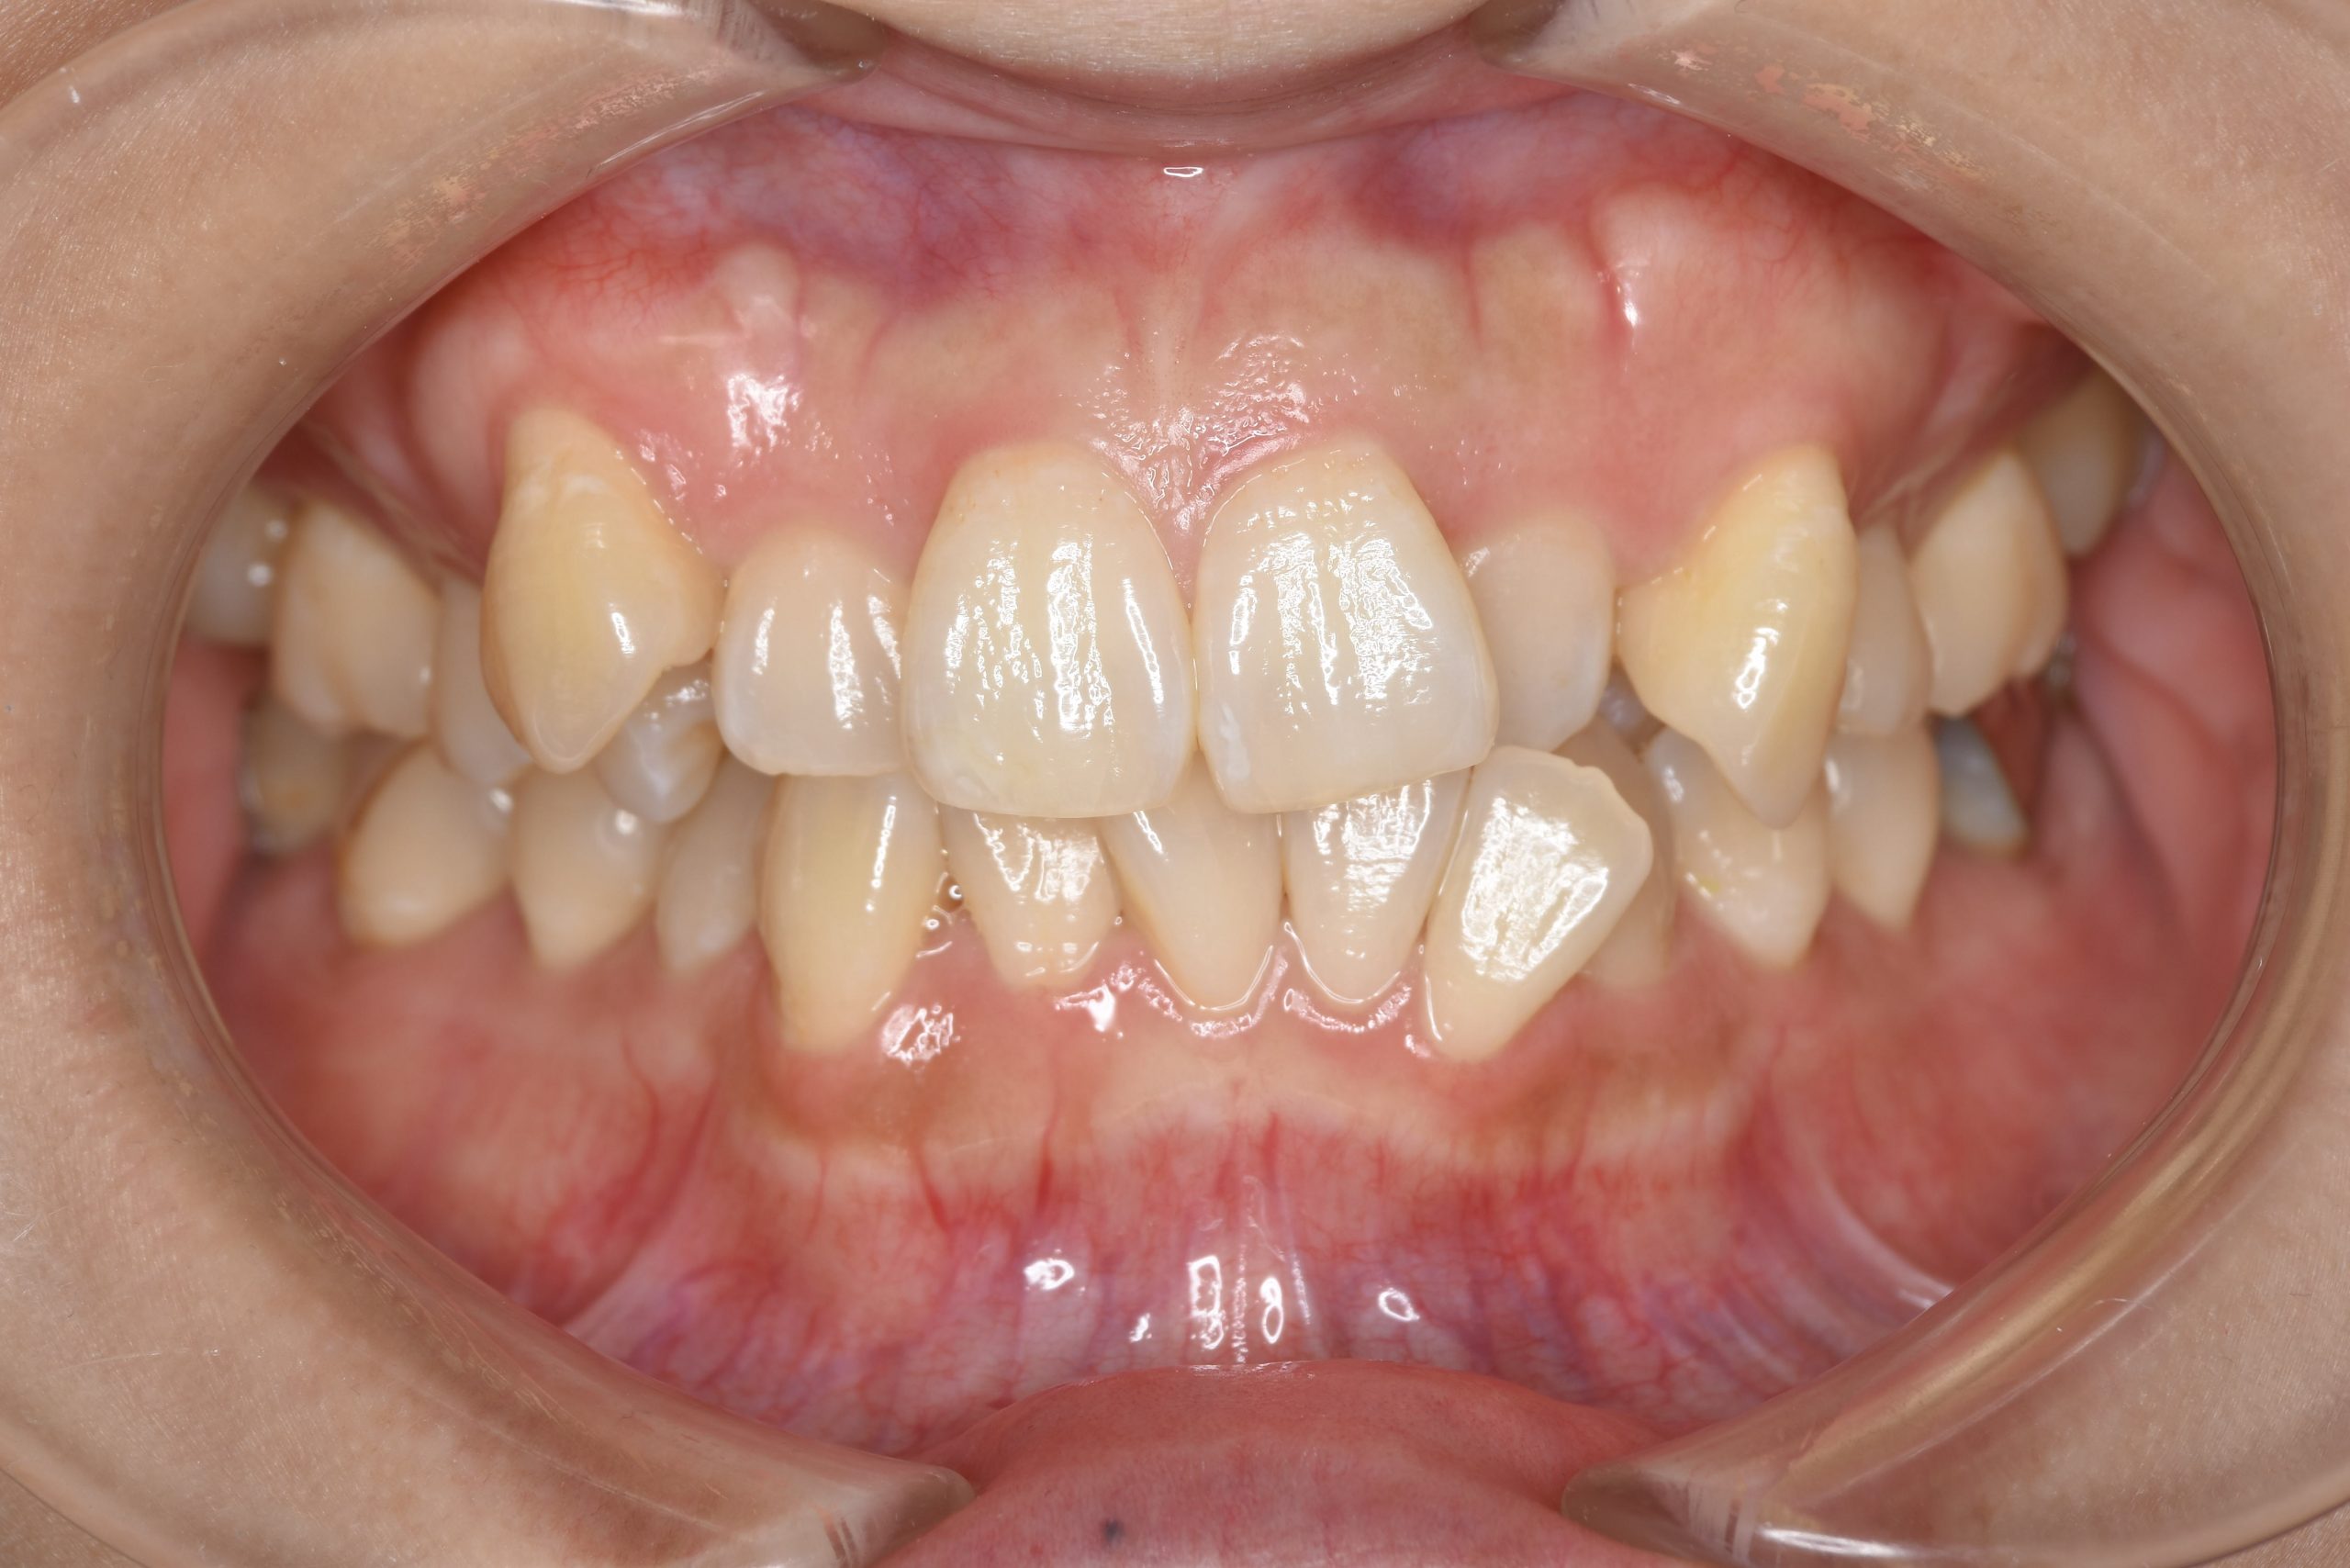

ビフォー

主訴 八重歯

施術内容 MSEと下顎リンガルアーチを用いて上下顎骨を拡大した。

その後上顎3・4番を抜歯しマルチブラケット装置とミニインプラントを用いて

歯牙を配列した。良好な咬合を獲得した。